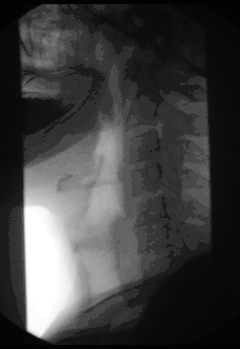

Fluoroscopy (/flʊəˈrɒskəpi/)[1], informally referred to as "fluoro", is an imaging technique that uses X-rays to obtain real-time moving images of the interior of an object. In its primary application of medical imaging, a fluoroscope (/ˈflʊərəˌskoʊp/)[2][3] allows a surgeon to see the internal structure and function of a patient, so that the pumping action of the heart or the motion of swallowing, for example, can be watched. This is useful for both diagnosis and therapy and occurs in general radiology, interventional radiology, and image-guided surgery.

Fluoroscopy has become an important tool in medical imaging to render moving pictures during a surgery or any other procedure.